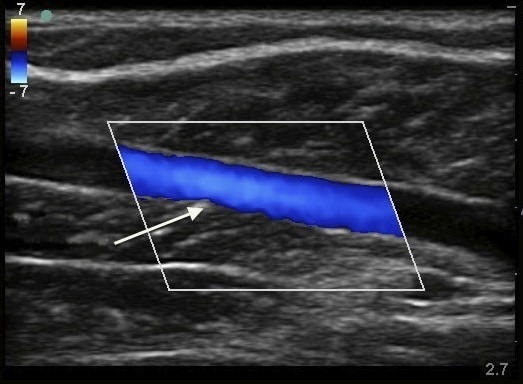

深部静脈血栓症 (DVT) 伏在静脈色イメージ